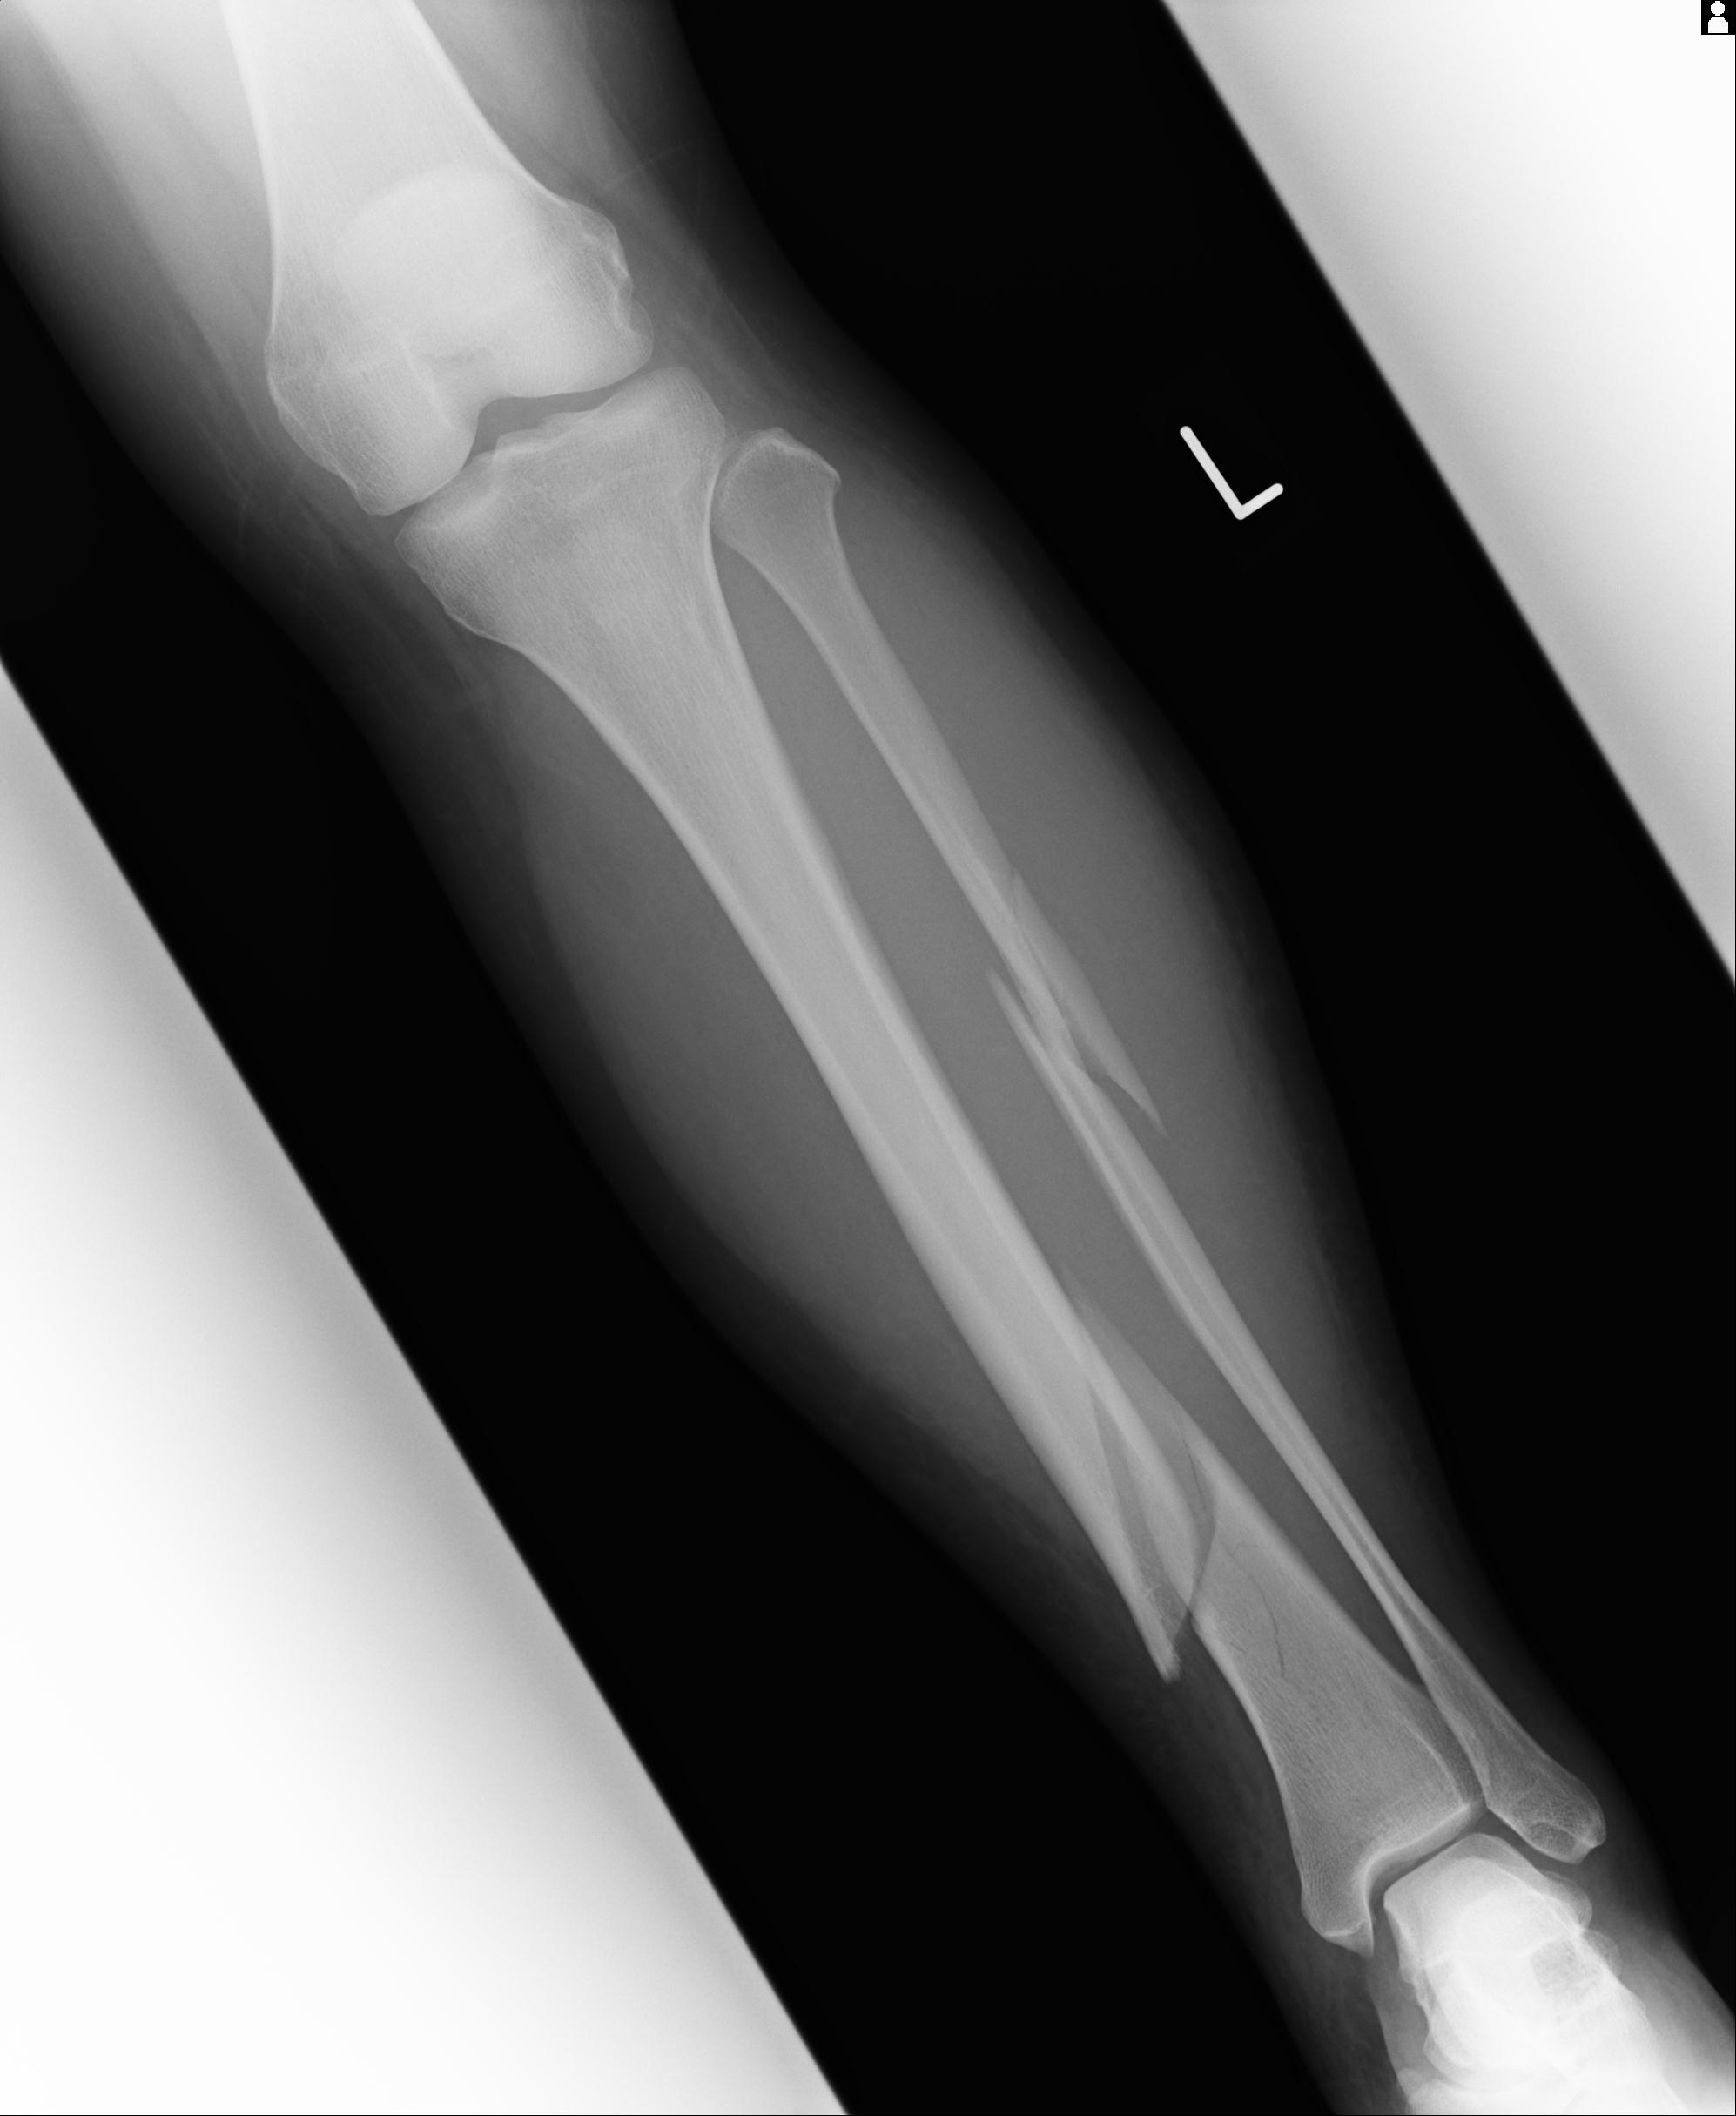

110211 1/6 1/8 左前腕 4R 15歳男性 橈骨骨幹部骨折